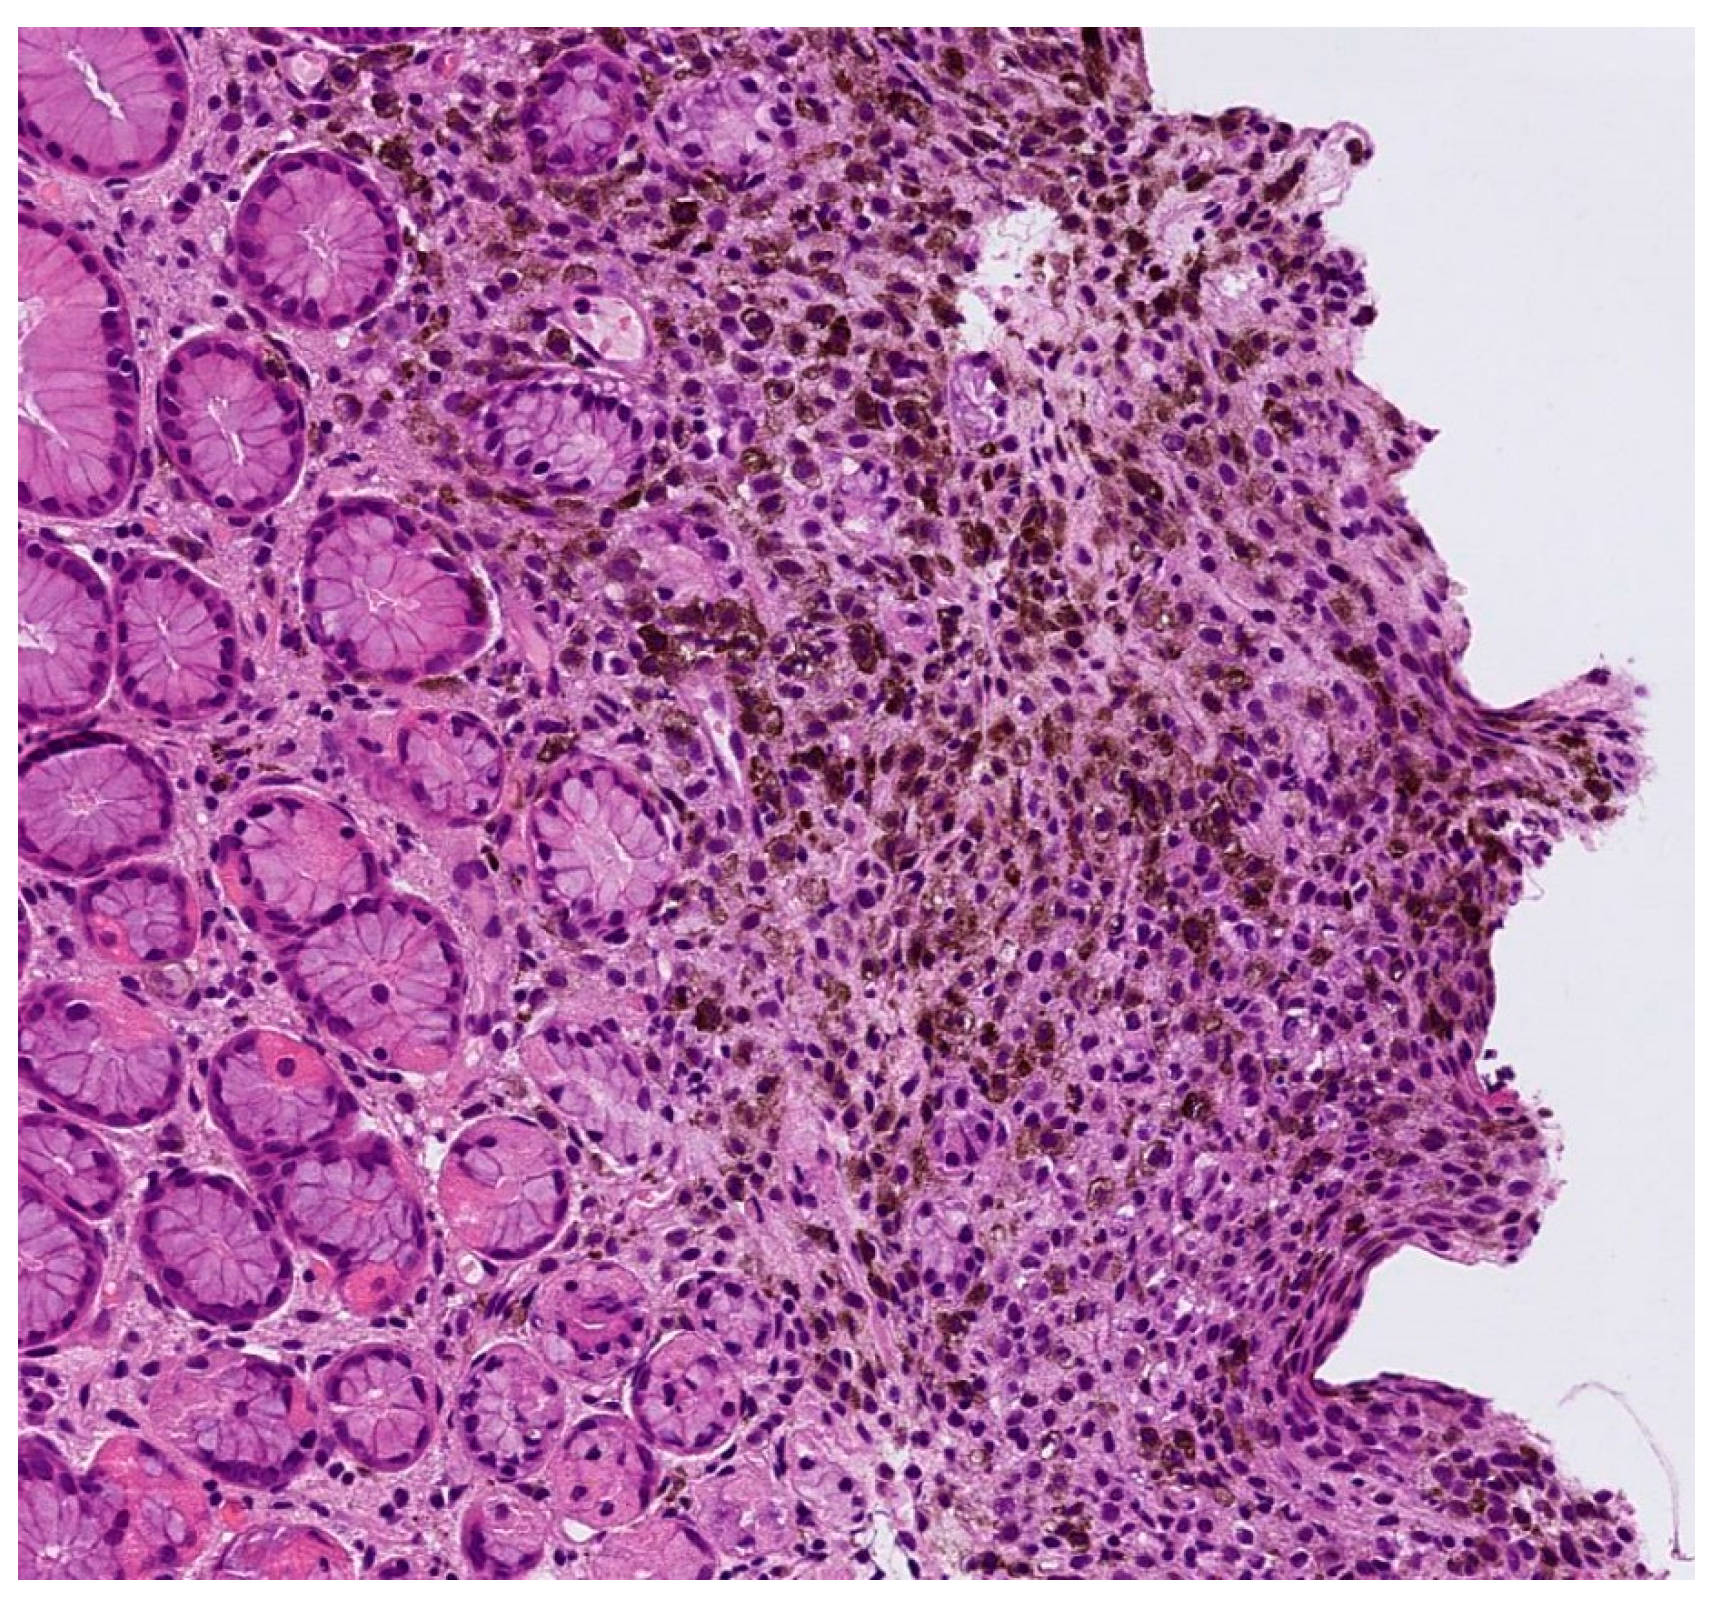

| 3 | 38/F | Blue nodule with agminated pigmentated macules | Homogenous violet-blue pattern with serpentine vessels | Desmoplastic blue nevus |